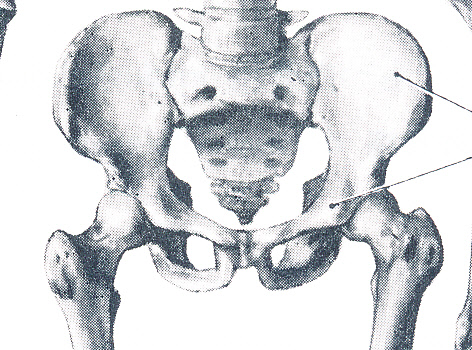

解剖学的には肩甲上腕関節は球関節に分類されますが、下肢は歩くことにほぼ特化されていますので関節は深い球関節になってがっちりと体重を支えています(図2)。上肢は色々な方向に動くため肩甲骨とは接している程度で浅い球関節になっています(図1、前々回 図2)。そのため肩関節のほうが脱臼しやすいのです。

出典:金子丑之助著「日本人体解剖学 第一巻」、南山堂、1956 図2.股関節